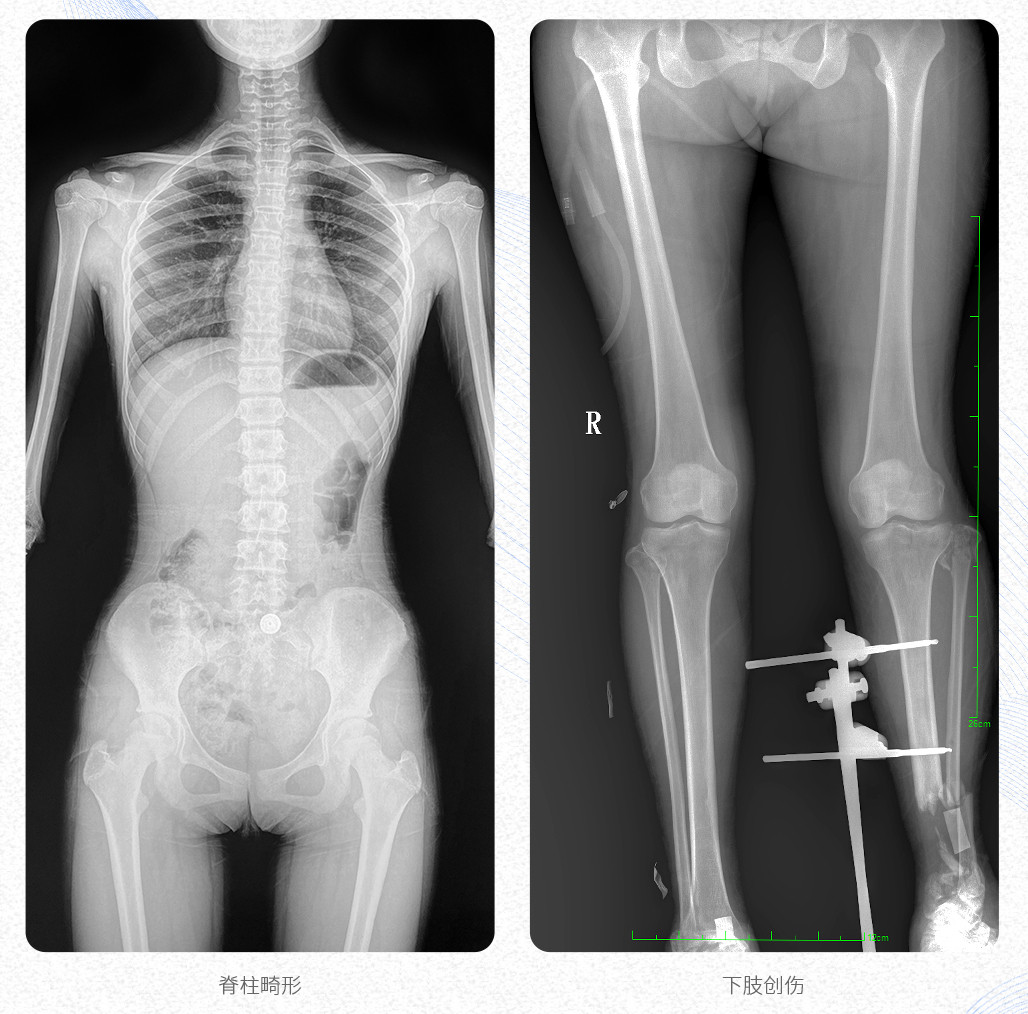

临床应用:支持全脊柱摄影、双下肢摄影、脊髓造影、复杂创伤、人工关节置换、关节损伤的修复重建等大视野临床应用。

17"*34"有效视野,是市面大尺寸平板的2倍,一次成像不拼接。相较于多张摄影再软件拼接的DR设备,PLX8600解决了拼接图像存在密度不均匀,拼接处图像配准和放大效应等问题,给临床带来了真正的大视野影像解决方案,高清画质,准确成像不失真,可一次性覆盖全脊柱或双下肢影像。PLX8600大视野平板动态DR摄影速度快,患者可以更快的完成检查,且单次摄影辐射剂量是常规多张摄影再软件拼接DR的1/2或1/3,低剂量给患者更多关爱。

除常规静态摄影外,PLX8600大平板具备动态透视和点片功能,透视采集功能可支持大视野、多角度的可视化观察。通过可视化的动态影像,配合点片功能,能够很好的观察复杂部位病灶,有效的抓取关键帧,降低患者多次摄片的概率,安全又高效。如:全脊柱状态评估、长骨关节活动度、下肢静脉造影瓣膜功能评估、消化道功能评估、脊髓造影等更多大视野临床应用,多面手给医生更多惊喜。

PLX8600大视野平板动态DR可在低辐射剂量下获得患者站立位、卧位的高质量影像。搭载自主研发的图像均衡处理系统,能够很好的均衡人体不同厚度组织的影像,视野大,图像清晰,层次丰富。